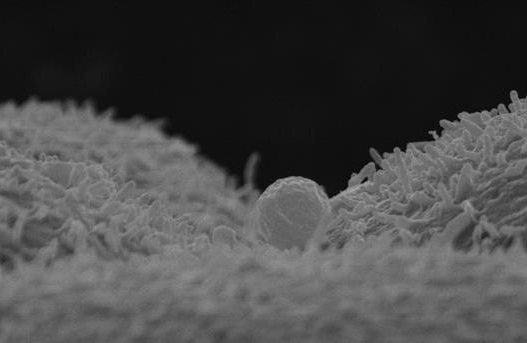

Electron microscope image showing a maternal exosome from human endometrial fluid binding to a mouse embryo cell. The embryo receives the contents of the maternal exosome to establish the first communication between the mother and the embryo in the period prior to implantation.

The study, carried out by researchers Doctor Felipe Viella and Doctor Carlos Simon from Fundación IVI the research arm of leading fertility clinic IVI, has demonstrated that expectant mothers can modify the genetic information of the child, even when the ovum is from a donor or between an expectant surrogate mother and baby. Viella and Simon observed the secretion of Hsa-miR-30-d by the human endometrium, which is subsequently taken up by the pre-implanted embryo influencing its development.